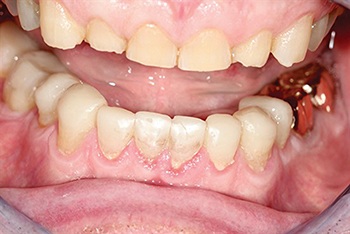

At delivery, the transformation was striking (Figs. 9–10). Incisal display returned, posterior support was reestablished, and aesthetics improved dramatically. McDermott tested his voice immediately after treatment, confirming that the restored occlusion supported his ability to continue singing.

Fig. 9: Immediate post-op smile

Fig. 10: Final full-face